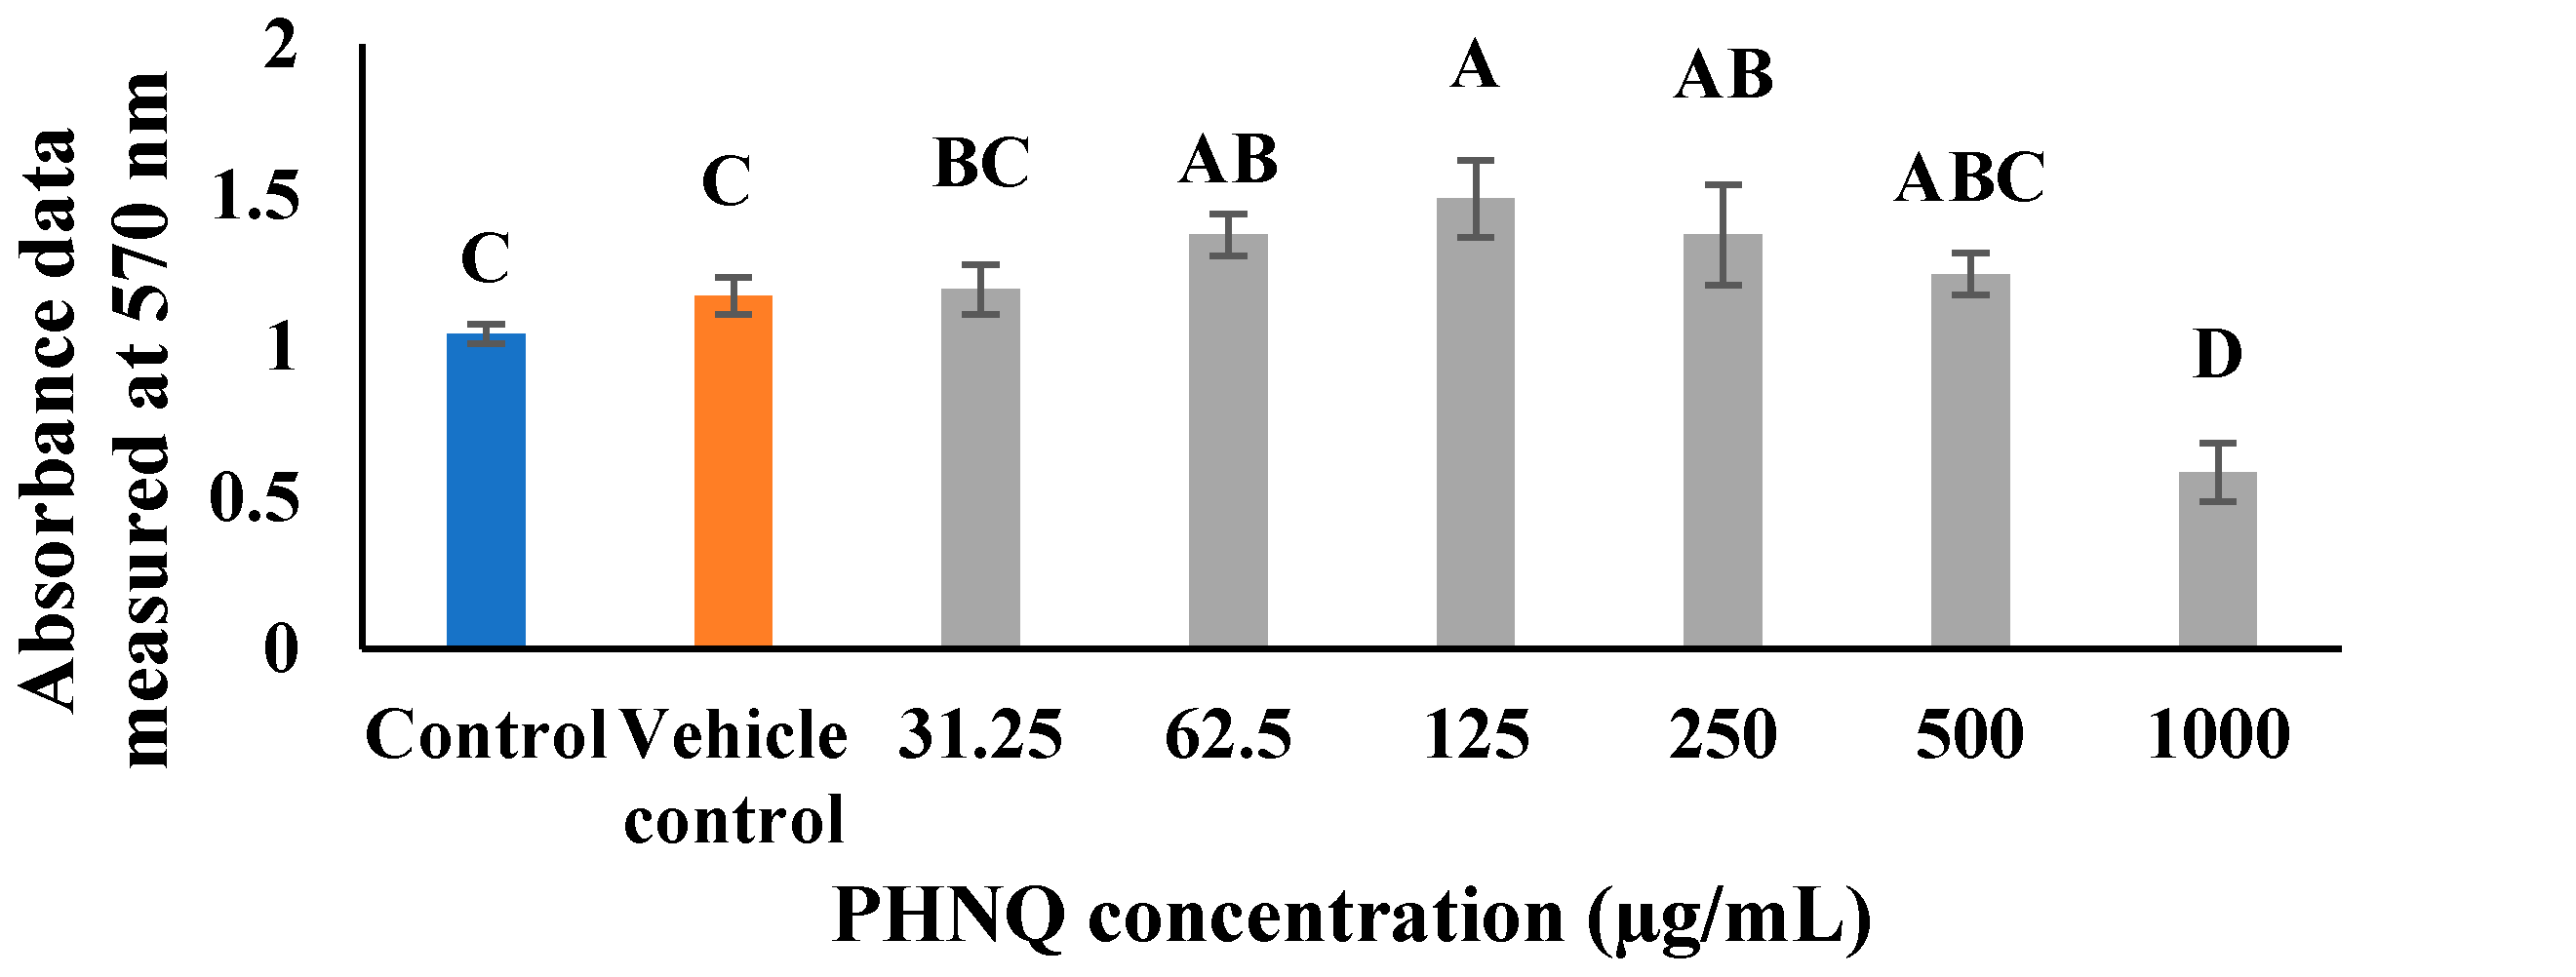

2.2. Cytotoxic Activity of E. chloroticus PHNQ Extract

4.4. Determination of Cytotoxicity of PHNQ by MTT Assay Using Saos-2 Cells (48 h Incubation Time)